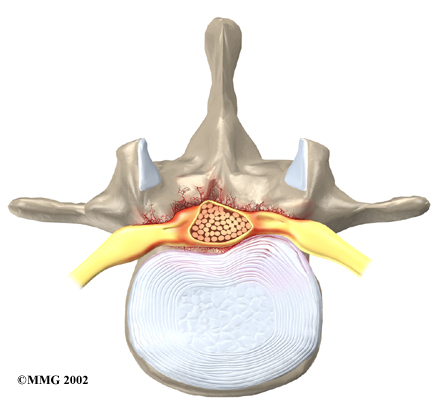

The back portion of the spinal column forms a bony ring. When the vertebrae are stacked on top of each other, these bony rings create a hollow tube. This bony tube, called the spinal canal, surrounds the spinal cord as it passes through the spine. Just as the skull protects the brain, the bones of the spinal column protect the spinal cord.

In the lumbar spine, the spinal canal usually has more than enough room for the spinal nerves. The canal is normally 17 to 18 millimeters around, slightly smaller than a penny. Spinal stenosis develops when the canal shrinks to 12 millimeters or less. When the size drops below 10 millimeters, severe symptoms of lumbar spinal stenosis occur.

Degeneration: Degeneration is the most common cause of spinal stenosis. Wear and tear on the spine from aging and from repeated stresses and strains can cause many problems in the lumbar spine. The intervertebral disc can begin to collapse, and the space between each vertebrae shrinks. Bone spurs may form that stick into the spinal canal and reduce the space available to the spinal nerves. The ligaments that hold the vertebrae together may thicken and also push into the spinal canal. All of these conditions cause the spinal canal to narrow.

Disc herniation: Spinal stenosis can occur when an intervertebral disc in the low back herniates (ruptures). Normally, the shock-absorbing disc is able to handle the downward pressure of gravity and the strain from daily activities. However, if the pressure on the disc is too strong, such as landing from a fall in a sitting position, the nucleus inside the disc may rupture through the outer annulus and squeeze out of the disc. This is called a disc herniation. If an intervertebral disc herniates straight backward, it can press against the nerves in the spinal canal, causing symptoms of spinal stenosis.

The lamina is the covering layer of the bony ring of the spinal column. It forms a roof-like structure over the back of the spinal canal. When the nerves in the spinal canal are being squeezed by a herniated disc or bone spurs, a lumbar laminectomy removes the entire lamina to release pressure on the spinal nerves. This is the primary type of surgery used for lumbar spinal stenosis.